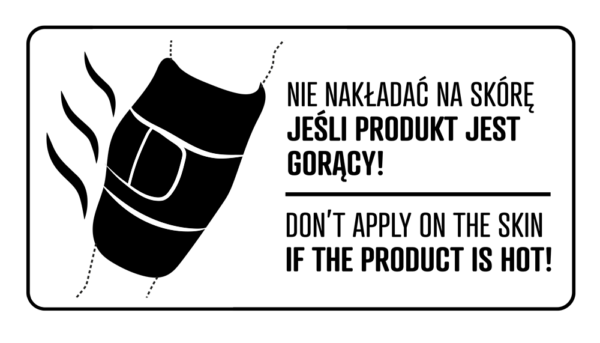

UWAGA! W przypadku występowania przewlekłego stanu zapalnego, zaleca się stosowanie worka w ramach terapii ciepłem. W tym celu należy napełnić worek gorącą wodą i przyłożyć w miejscu bólu. Wówczas worek działa jak termofor, zmniejsza dolegliwości bólowe, ma działanie rozluźniające i rozkurczające.

To jest wyrób medyczny.

Używaj go zgodnie z instrukcją używania lub etykietą.